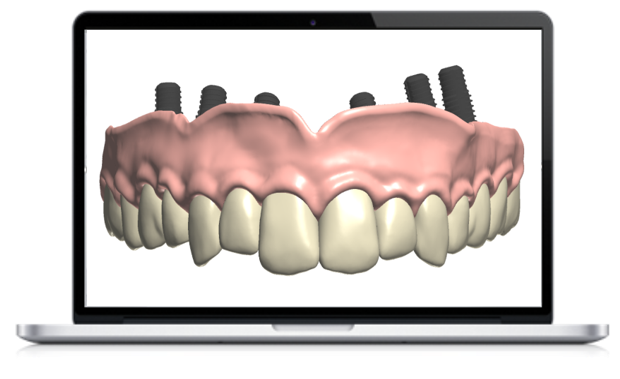

“In the private practice I work in, my surgeon does not touch a single implant without guided surgery. Because it is so much more predictable and safer and faster. Planning is done behind the scenes, which makes us safer chairside.

Digital workflows enable us to work as a group. My surgeon and I can design a surgery. We can work on the surgical and restorative concept together and print or mill a surgical guide to make the procedure more predictable. We prosthetically plan our implant procedure on a PC.

Implants placed using guided surgery are much safer and more predictable in my view.

Personally, if I need an implant, I’m going to someone who does guided surgery. From my experiences, I am no longer interested in freehand.

In fact, I would say a doctor that uses guides is more predictable. So going digital is not about being young or progressive, but about being a more predictable and maybe ever more accurate. Plus, your results are going to be faster.